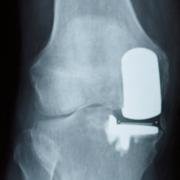

PKR is an abbreviation of 'partial knee replacement'.

A partial knee replacement may involve any one of these compartments.

Patient not settling after unicondylar replacement.